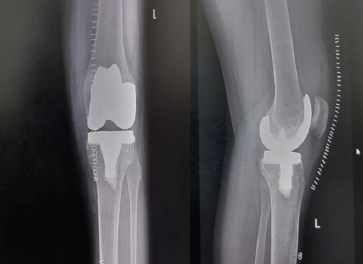

Flexor Carpi Radialis Tendon Stabilization for Chronic First Carpometacarpal Joint Instability: Clinical Outcomes from a Case Report

Akshay Punekar , Santosh D Ghoti , Mohammed Amjad Sohiel , Niranjan Sunil Ghag , Alok Yadav , Aditya A Agarwal